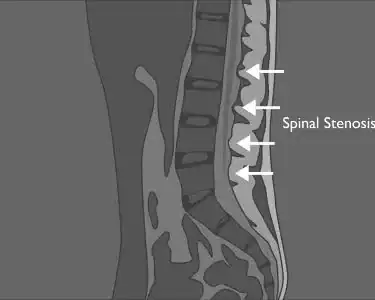

How to

Read a Lumbar MRI